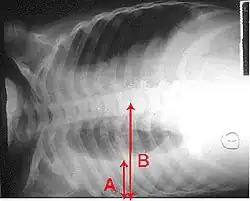

The World Health Organization has defined pneumonia in children clinically based on either a cough or difficulty breathing and a rapid respiratory rate, chest indrawing, or a decreased level of consciousness.[65] A rapid respiratory rate is defined as greater than 60 breaths per minute in children under 2 months old, greater than 50 breaths per minute in children 2 months to 1 year old, or greater than 40 breaths per minute in children 1 to 5 years old.[65]

In children, low oxygen levels and lower chest indrawing are more sensitive than hearing chest crackles with a stethoscope or increased respiratory rate.[66] Grunting and nasal flaring may be other useful signs in children less than five years old.[67]